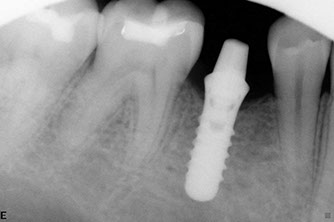

Successful treatment of a complicated molar with four canals by Dr. Young

• Dental implants

Dental implants have been used for decades to provide a stable support for missing teeth. Implants can be used to stabilize dentures, act as anchors for a bridge, or replace single teeth that are missing.

Implants are designed to be incorporated into the structure of the jawbone. A crown is then attached to the implant to function as a normal tooth. In most cases, implants take several months from placement to the final restoration(s). There is a period of healing while the implant becomes part of the body and stabilizes.